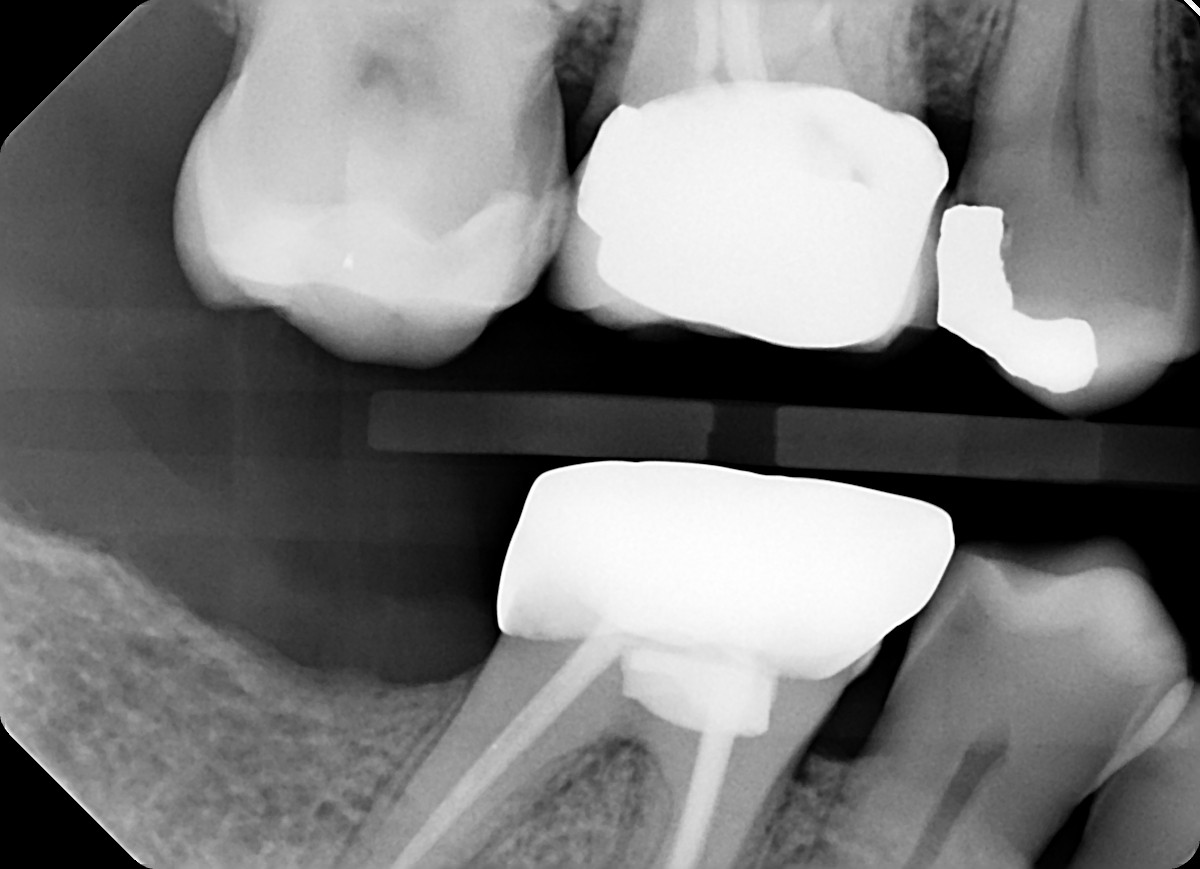

4. What option can explain the crown of the tooth #4.7?